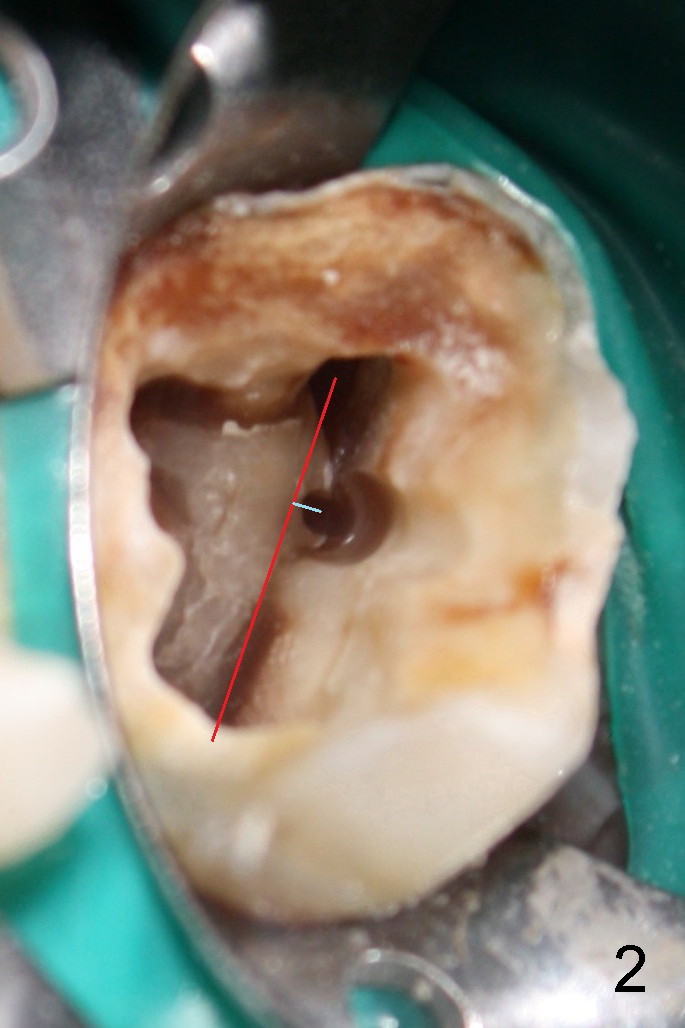

第一:MB2在MB1舌侧1-3毫米,如果在MB1和P之间画一条线(图二红线),MB2又在红线近中0.5毫米,淡蓝色线与红线垂直。

第三:对所有上颌磨牙应该常规寻找MB2,花不了太多时间,也不难,也就是在MB1和P之间黑线(map),用超声波Piezo tip往根尖方向去除牙本质1-4毫米。如果黑线消失,说明是侧枝根管,不必继续探索。